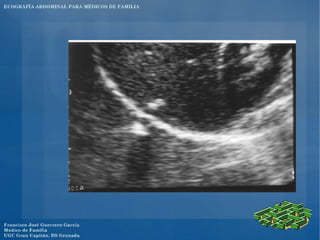

El documento presenta un programa de ecografía abdominal para médicos de familia que incluye presentaciones sobre generalidades de la ecografía y anatomía normal de los órganos abdominales los jueves, y sobre imágenes anormales en ecografía abdominal y ecografía obstétrica los viernes, con un caso clínico el sábado en el centro.